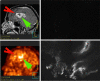

Purpose: The primary purpose of this study was to assess the biodistribution and radiation dose resulting from administration of (18)F-EF5, a lipophilic 2-nitroimidazole hypoxia marker in ten cancer patients. For three of these patients (with glioblastoma) unlabeled EF5 was additionally administered to allow the comparative assessment of (18)F-EF5 tumor uptake with EF5 binding, the latter measured in tumor biopsies by fluorescent anti-EF5 monoclonal antibodies.

Methods: (18)F-EF5 was synthesized by electrophilic addition of (18)F(2) gas, made by deuteron bombardment of a neon/fluorine mixture in a high-pressure gas target, to an allyl precursor in trifluoroacetic acid at 0° then purified and administered by intravenous bolus. Three whole-body images were collected for each of ten patients using an Allegro (Philips) scanner. Gamma counts were determined in blood, drawn during each image, and urine, pooled as a single sample. PET images were analyzed to determine radiotracer uptake in several tissues and the resulting radiation dose calculated using OLINDA software and standard phantom. For three patients, 21 mg/kg unlabeled EF5 was administered after the PET scans, and tissue samples obtained the next day at surgery to determine EF5 binding using immunohistochemistry techniques (IHC).

Results: EF5 distributes evenly throughout soft tissue within minutes of injection. Its concentration in blood over the typical time frame of the study (∼3.5 h) was nearly constant, consistent with a previously determined EF5 plasma half-life of ∼13 h. Elimination was primarily via urine and bile. Radiation exposure from labeled EF5 is similar to other (18)F-labeled imaging agents (e.g., FDG and FMISO). In a de novo glioblastoma multiforme patient, focal uptake of (18)F-EF5 was confirmed by IHC.

Conclusion: These results confirm predictions of biodistribution and safety based on EF5's characteristics (high biological stability, high lipophilicity). EF5 is a novel hypoxia marker with unique pharmacological characteristics allowing both noninvasive and invasive measurements.